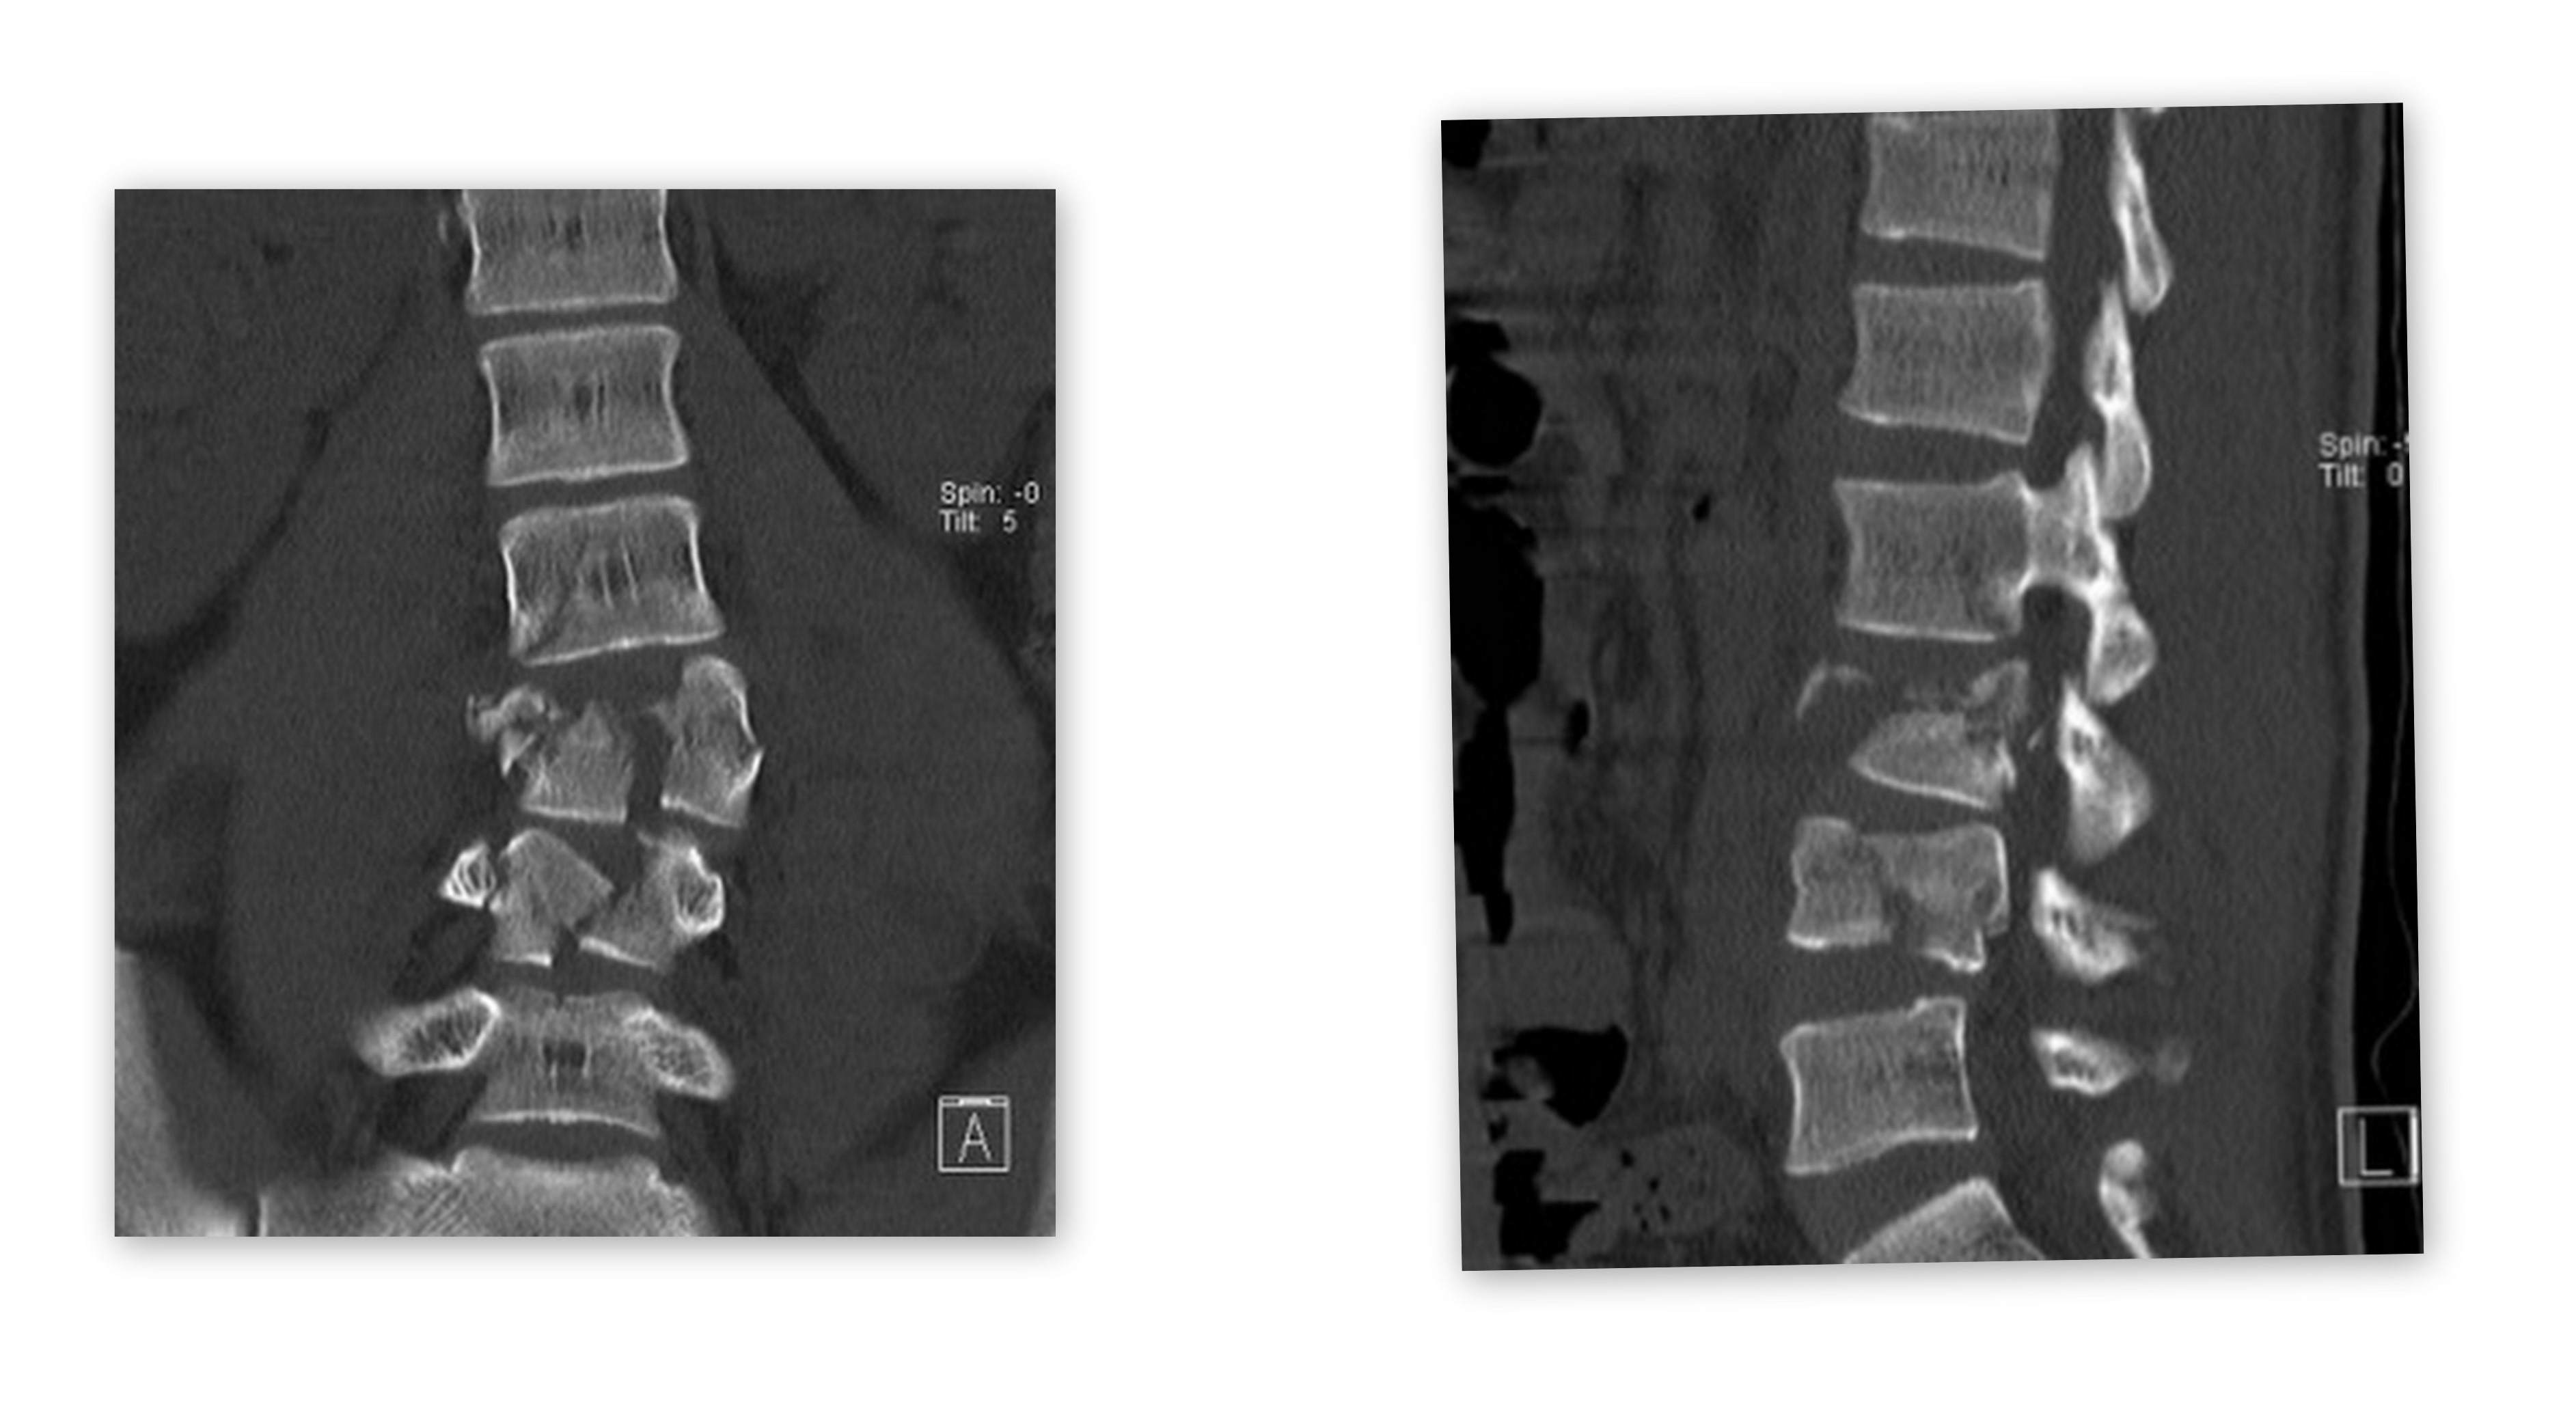

伤者术前X光片

患者是一名民工,今年只有19岁。日前在天津静海县一工地施工中不慎从3米高的工地上坠落,导致严重腰椎骨折。入院时患者双下肢瘫痪,左小腿肌力0肌,右小腿肌力1肌。小便潴留需要下导尿管排尿。术前CT检查示 腰椎3.4椎体爆裂骨折,骨折碎片凸入椎管, 腰3椎板椎弓根骨折,腰4右侧椎弓根骨折。腰2椎体骨折椎板骨折,腰5椎板骨折。患者腰椎冠状位及矢状位脱位。骨科值班医生亢卫波,紧急安排患者做急诊住院相关检查。骨科副主任医师李家谋博士当晚查看病人,及时向科主任汇报了病情。